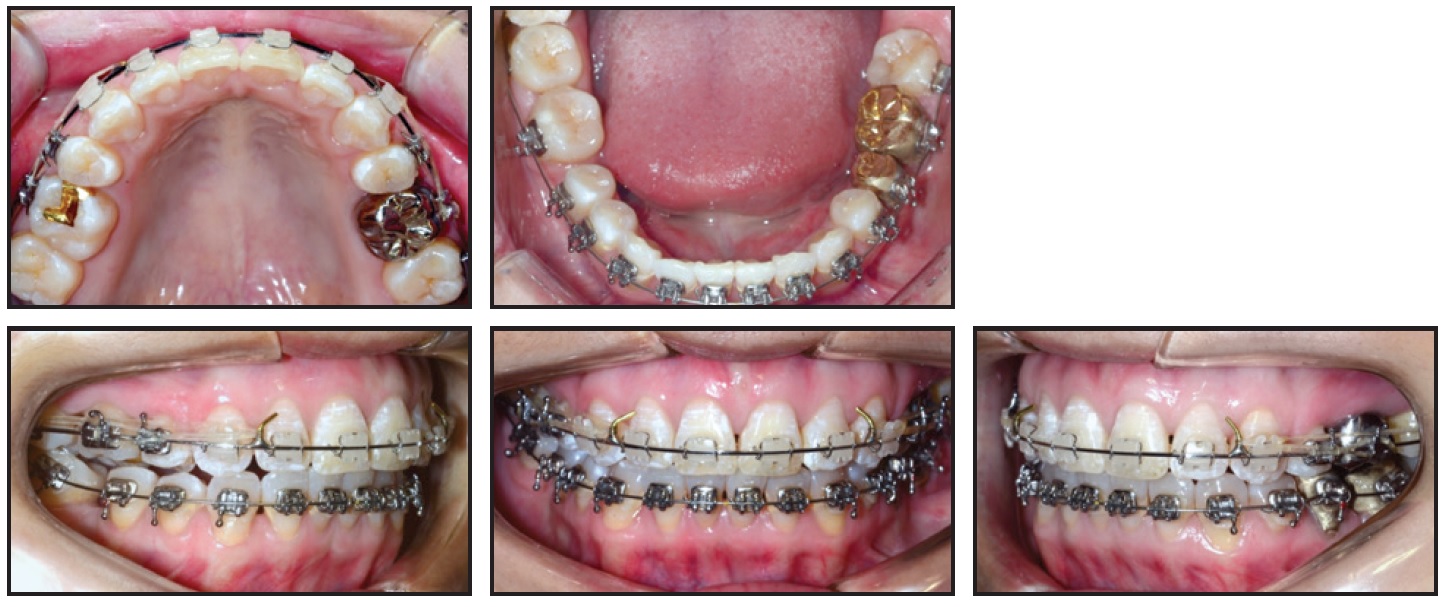

At the end of orthodontic treatment, porcelain crown prostheses were placed to reestablish the form of the lower central incisors. A passive upper retainer for long-term nighttime wear was fabricated from Copyplast*** C using a MiniSTAR S,*** and a lower 3-3 lingual retainer was bonded.

Total treatment time was 35 months (Fig. 5). The balanced profile and Class I canine and molar relationships were successfully maintained, and the patient was highly satisfied with his teeth and profile. The mandibular incisors were aligned, with the proper torque. The skeletal maxillomandibular relationship was slightly improved, the maxillary incisors were slightly proclined, and the mandibular incisors were uprighted (Table 1). The overjet and overbite were reduced, and the upper and lower lip positions and nasolabial angle were basically unchanged.

Fig. 5 Patient after 35 months of treatment (records taken seven months later).